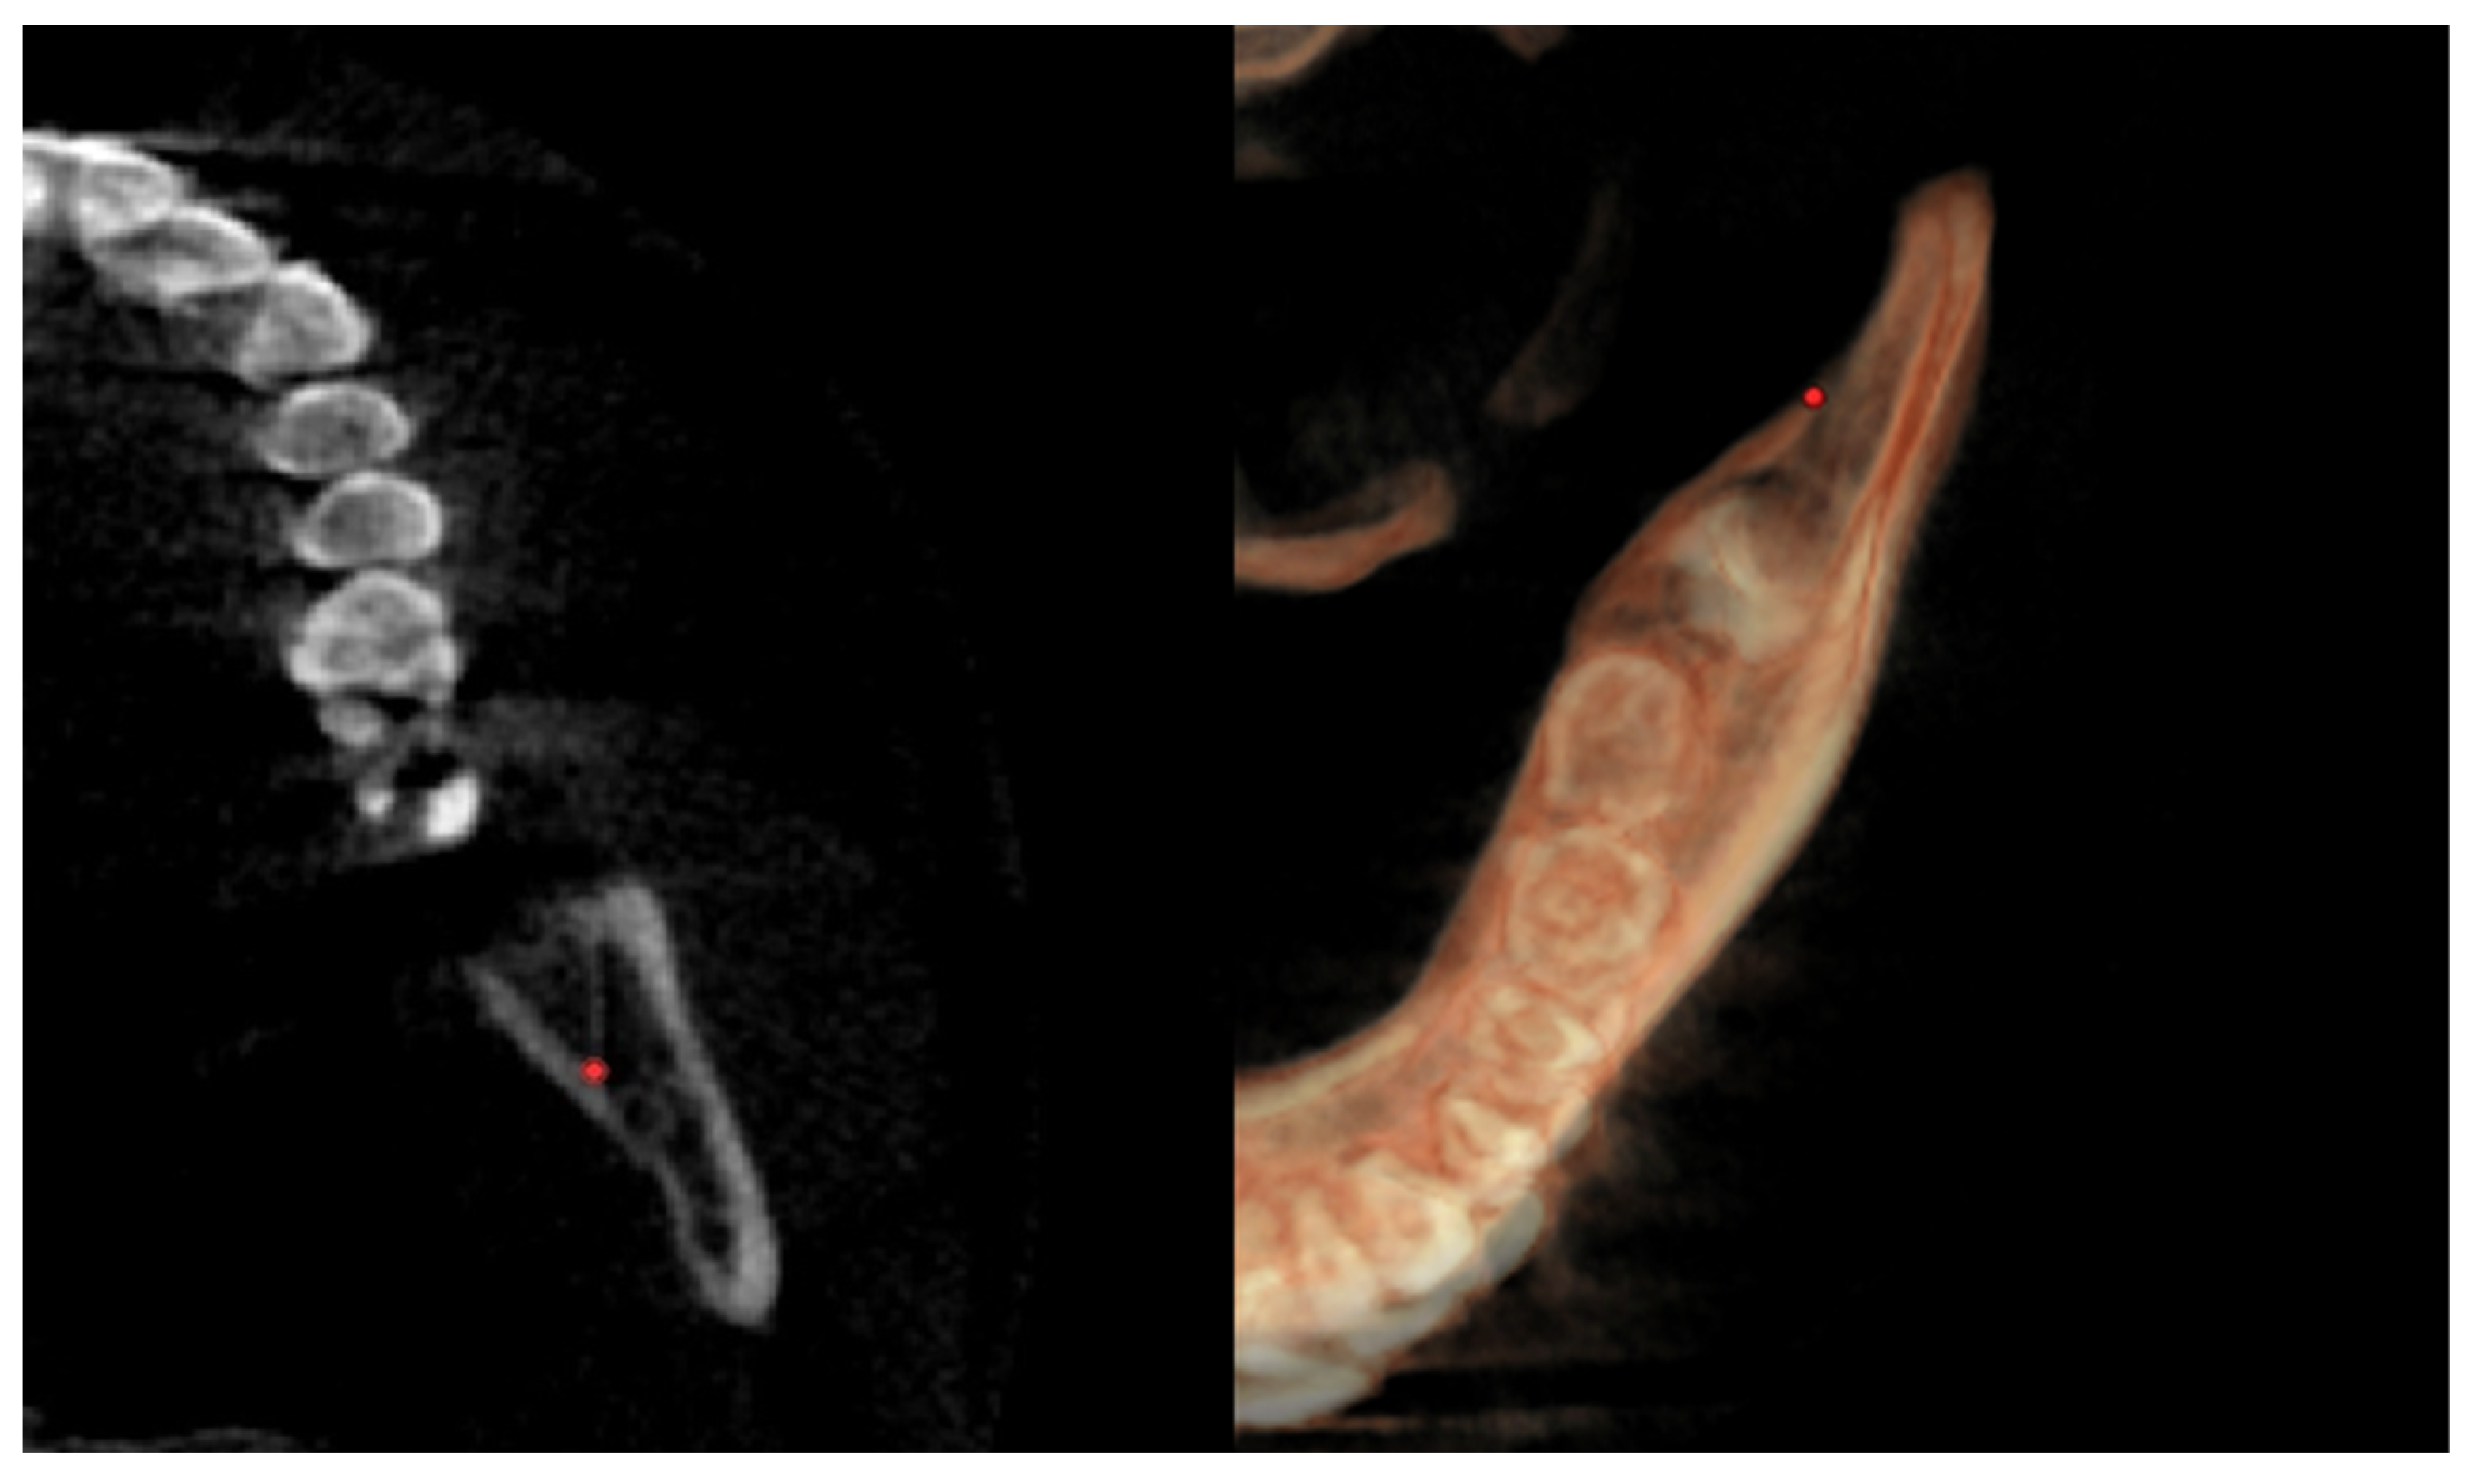

| Right lingual tuberosity (rLT) | / | The most posterior point (apex) of the retromandibular triangle, right side (Figure 5) | / |

| Left lingual tuberosity (lLT) | / | The most posterior point (apex) of the retromandibular triangle, left side (Figure 5) | / |